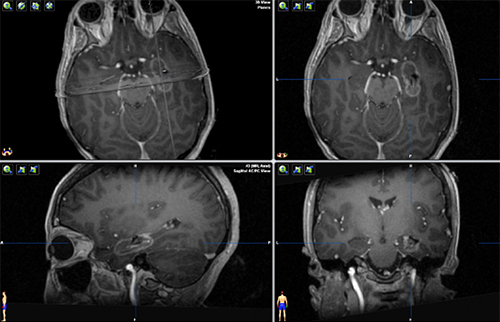

Postoperative MRI with contrast demonstrating a completed ablation for drug resistant mesial temporal lobe epilepsy. The patient went home the day after surgery and remains seizure free more than 2 years later.

MRg-LITT is the selective ablation of a lesion or a structure using heat from a laser. Once an ablation target is identified, one or more laser fiber trajectories are planned based on the target, adjacent and overlying anatomy, and estimates of thermal spread. The laser fiber is placed with stereotactic image guidance though a less than 1cm incision. During the ablation, temperature is monitored in real-time in the MRI scanner to prevent damage to nearby structures. Patients frequently go home the next day after the procedure.